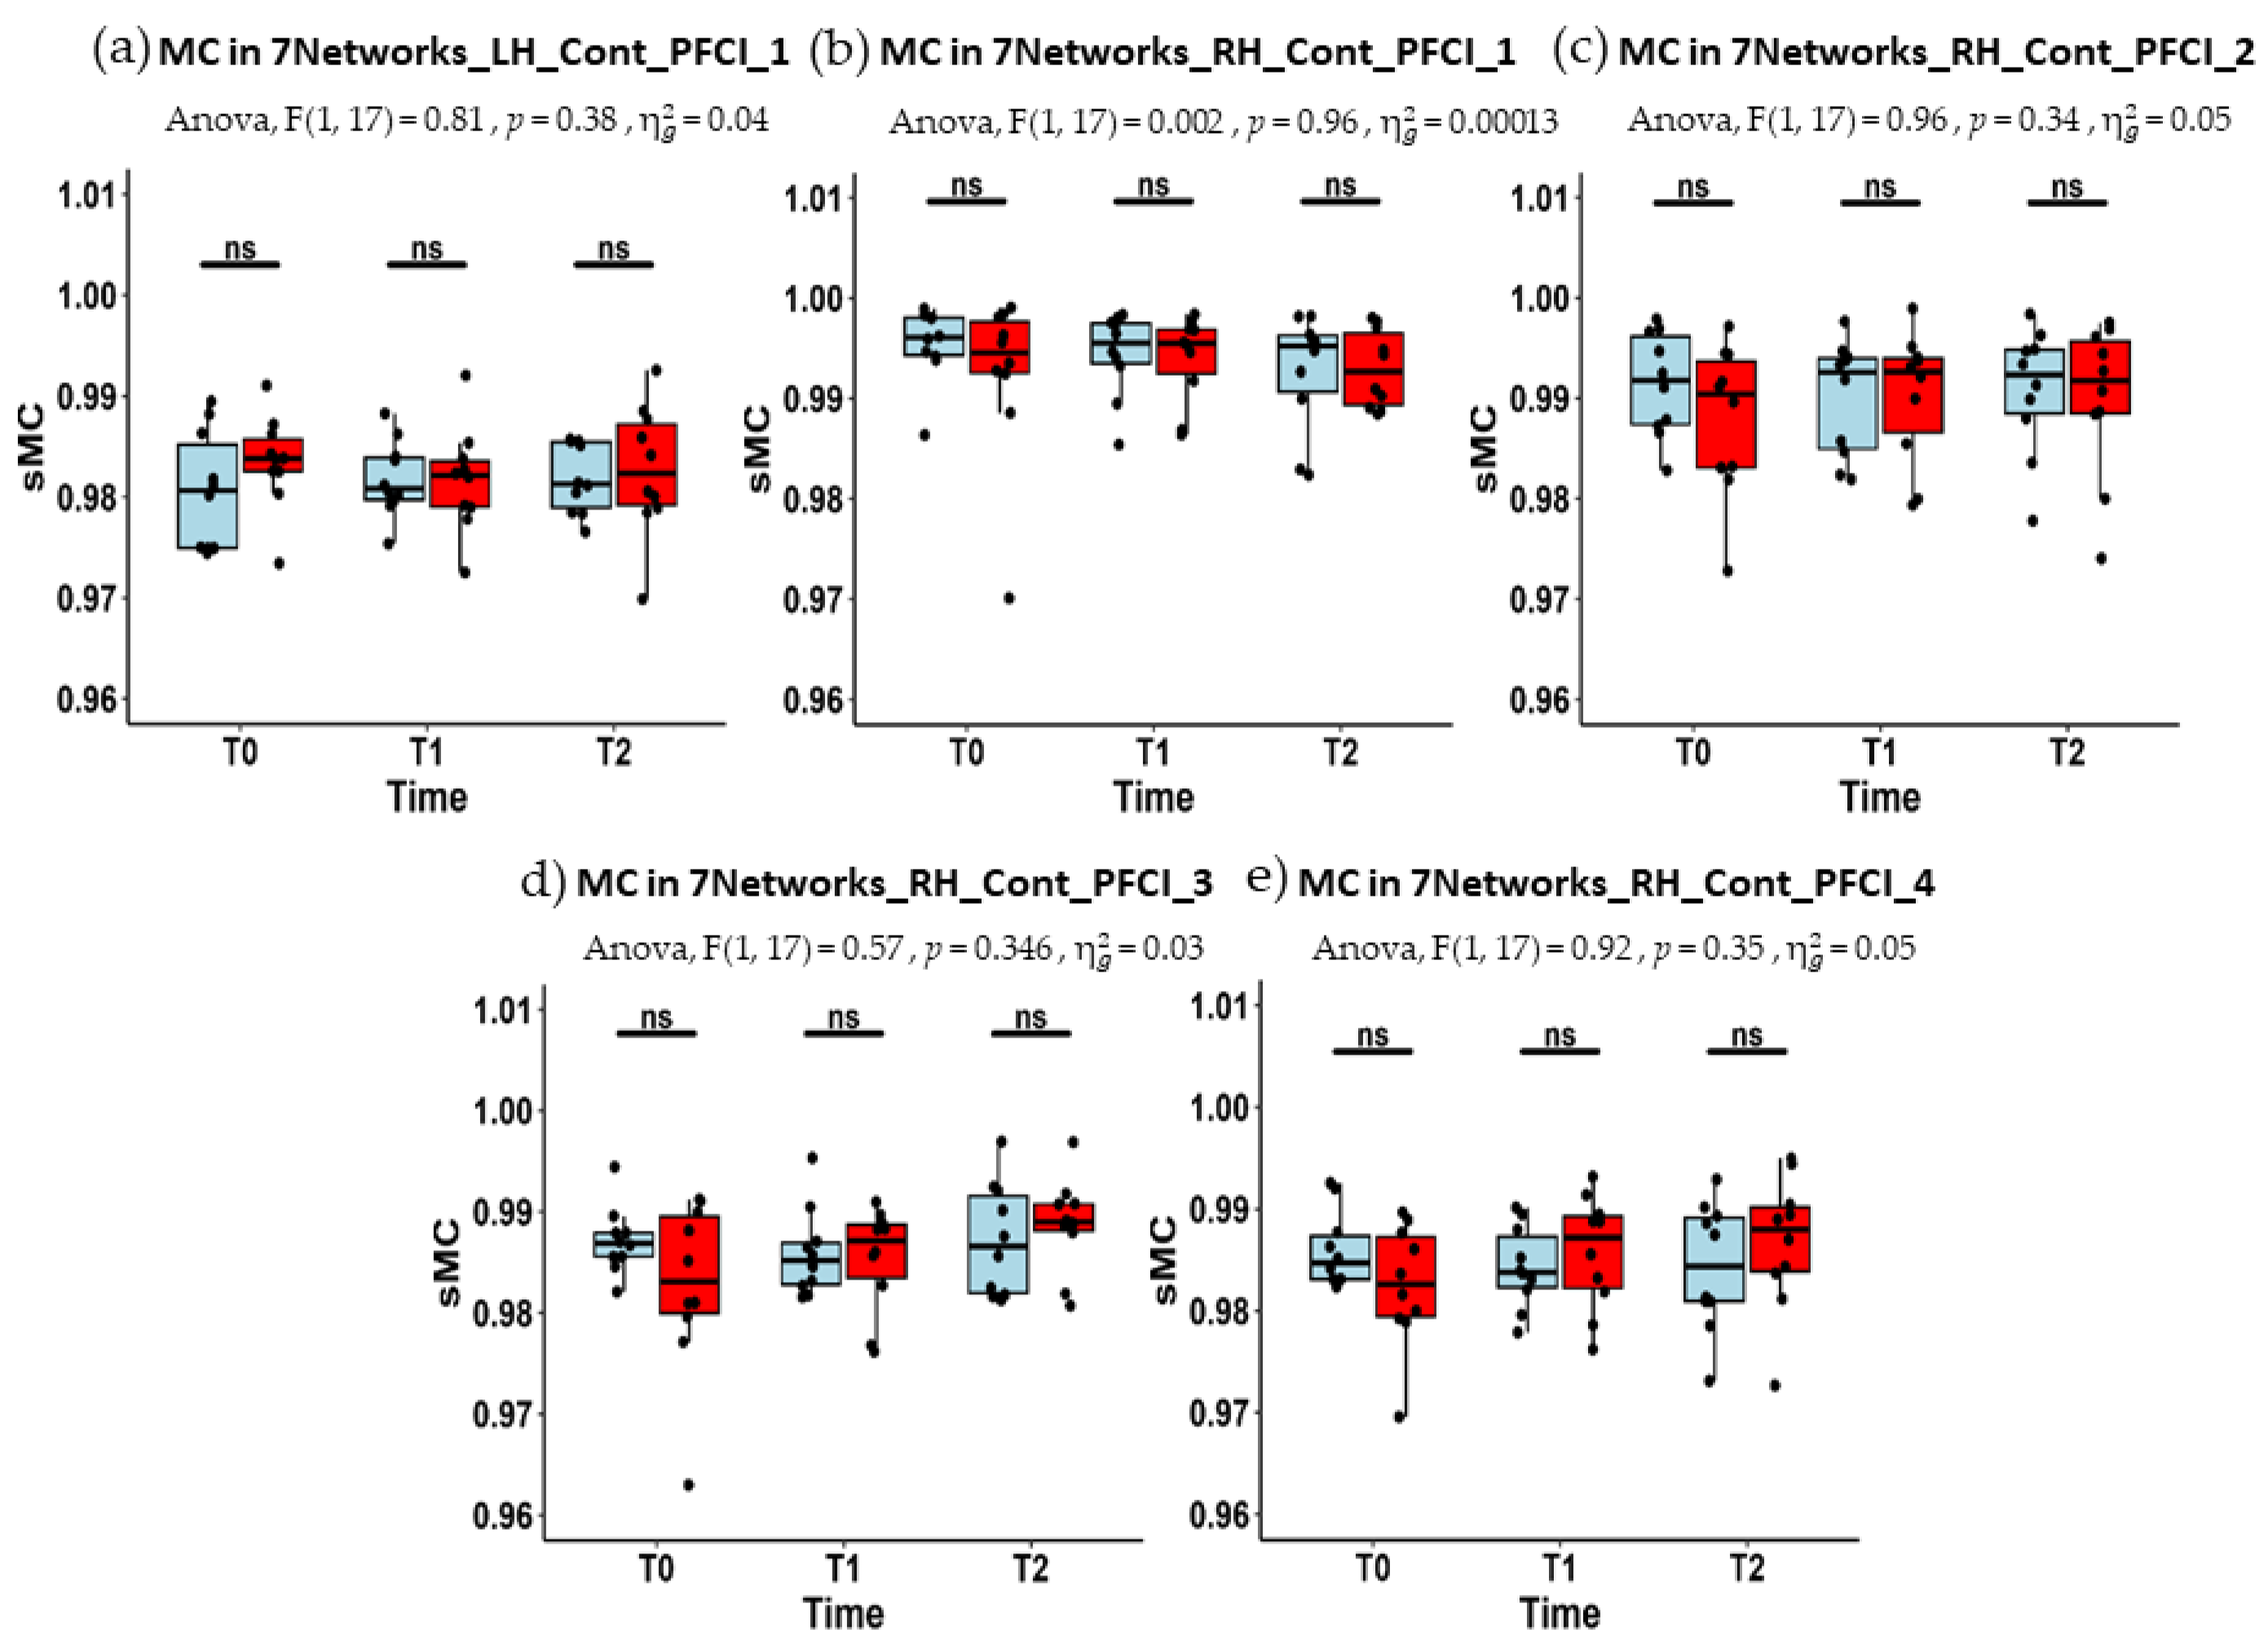

| LH_Cont_PFCl_1 | 0.981 (0.975–0.985) | 0.981 (0.980–0.984) | 0.981 (0.979–0.985) |

| RH_Cont_PFCl_1 | 0.996 (0.994–0.998) | 0.996 (0.993–0.997) | 0.995 (0.991–0.996) |

| RH_Cont_PFCl_2 | 0.992 (0.987–0.996) | 0.993 (0.985–0.994) | 0.992 (0.988–0.995) |

| RH_Cont_PFCl_3 | 0.987 (0.986–0.988) | 0.985 (0.983–0.987) | 0.987 (0.982–0.992) |

| RH_Cont_PFCl_4 | 0.985 (0.983–0.987) | 0.984 (0.982–0.987) | 0.984 (0.981–0.989) |

| LH_Cont_PFCl_1 | 0.984 (0.983–0.986) | 0.982 (0.979–0.984) | 0.982 (0.979–0.984) |

| RH_Cont_PFCl_1 | 0.995 (0.993–0.998) | 0.995 (0.992–0.997) | 0.993 (0.989–0.997) |

| RH_Cont_PFCl_2 | 0.990 (0.983–0.994) | 0.993 (0.987–0.994) | 0.992 (0.988–0.996) |

| RH_Cont_PFCl_3 | 0.983 (0.980–0.990) | 0.987 (0.983–0.989) | 0.989 (0.988–0.991) |

| RH_Cont_PFCl_4 | 0.983 (0.979–0.987) | 0.987 (0.982–0.989) | 0.988 (0.984–0.990) |